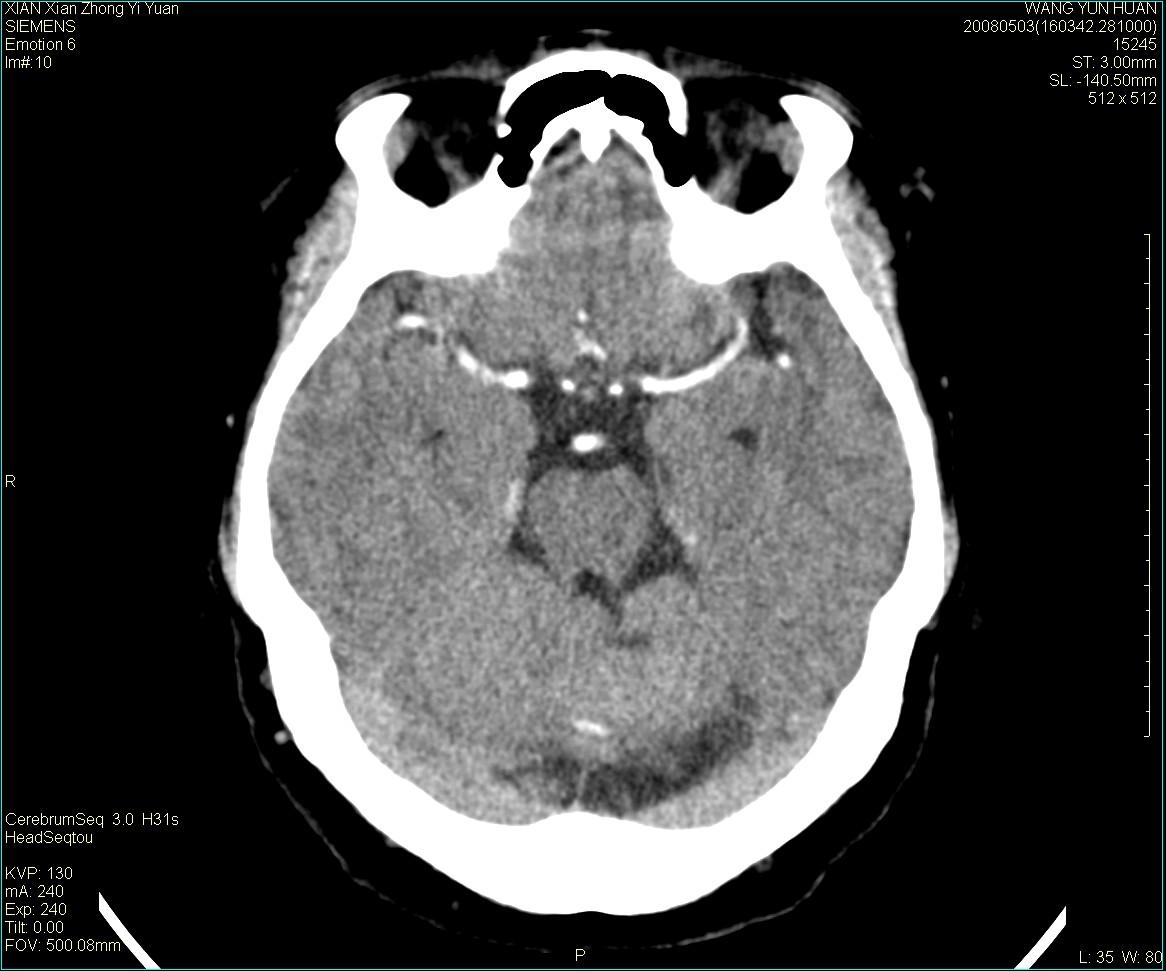

病灶显示轻度强化,ct增加4hu左右,大家看是什么肿瘤.

强化后动脉期及延迟2分钟,五分钟图像

小脑蚓部囊型肿块,内有实性结节及钙化点。增强后囊壁及结节轻度强化。

考虑蚓部星形细胞瘤(ⅱ级可能性大)。

小脑蚓部肿块,周围无明显占位效应及水肿带,增强轻度强化,考虑低分级星形细胞瘤。